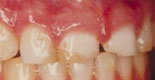

Före och efter behandling med fyra keramiska skalfasader.